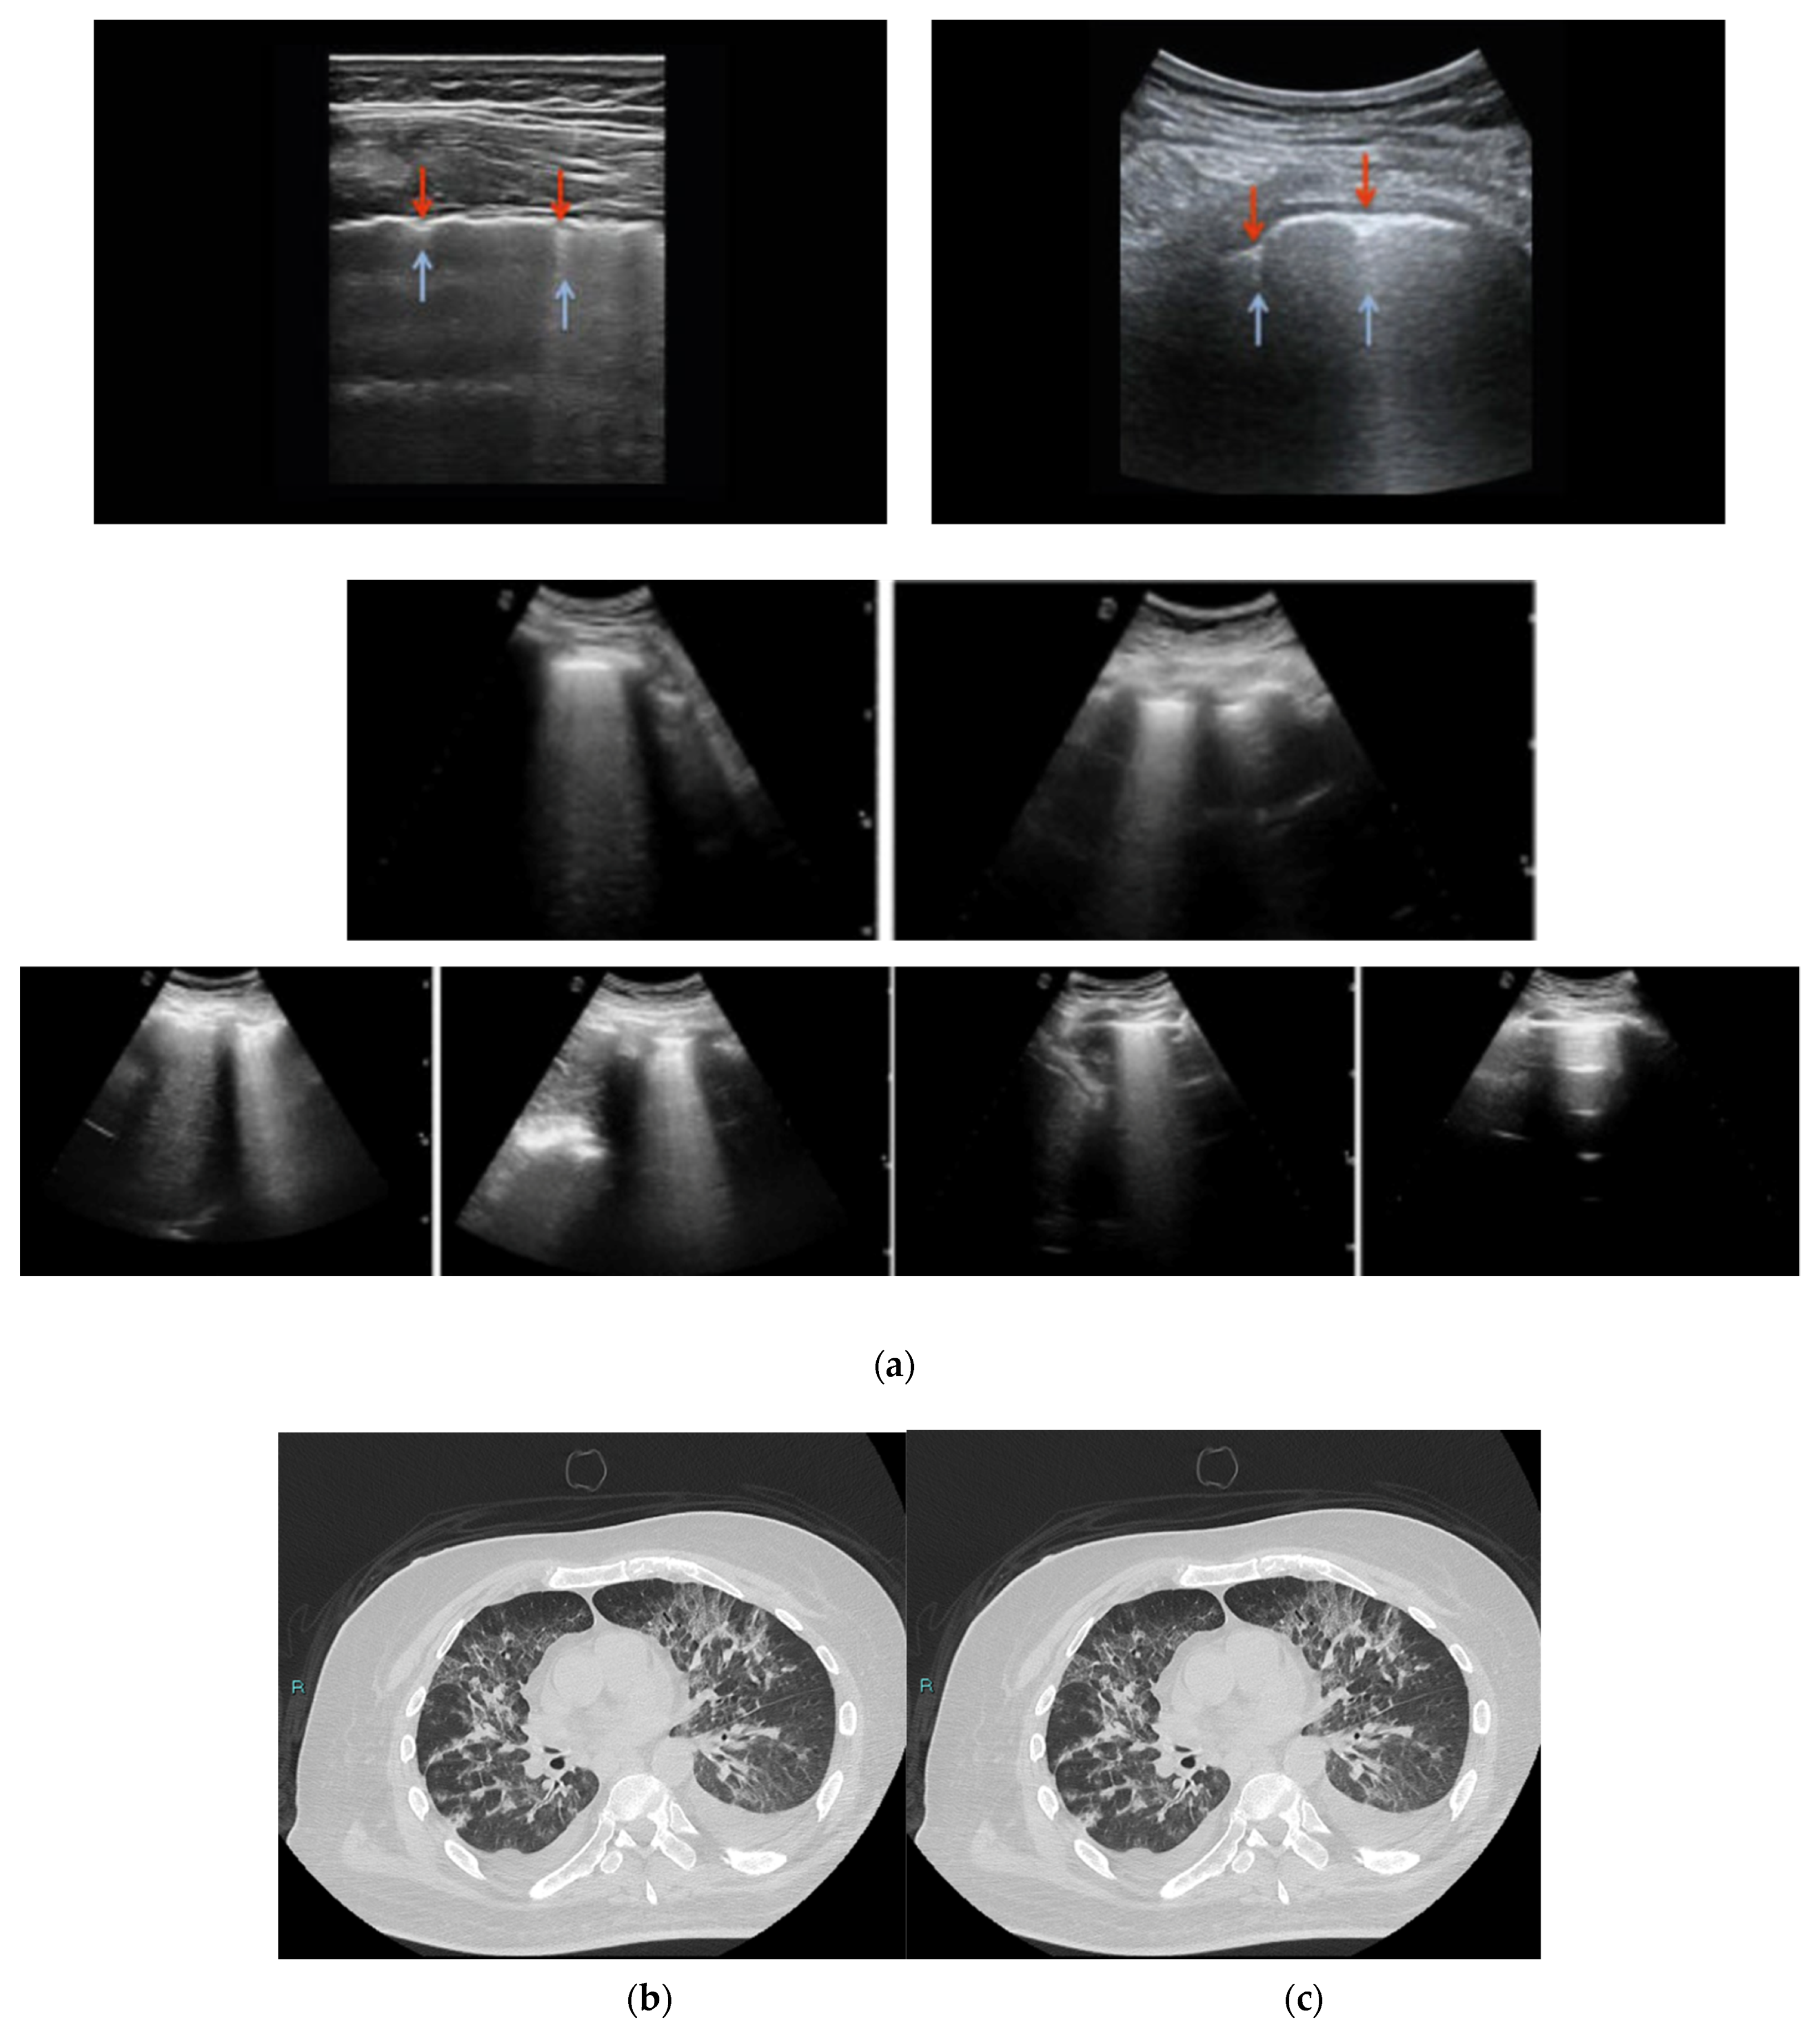

2.6. High Resolution CT (HRCT)

3. Results